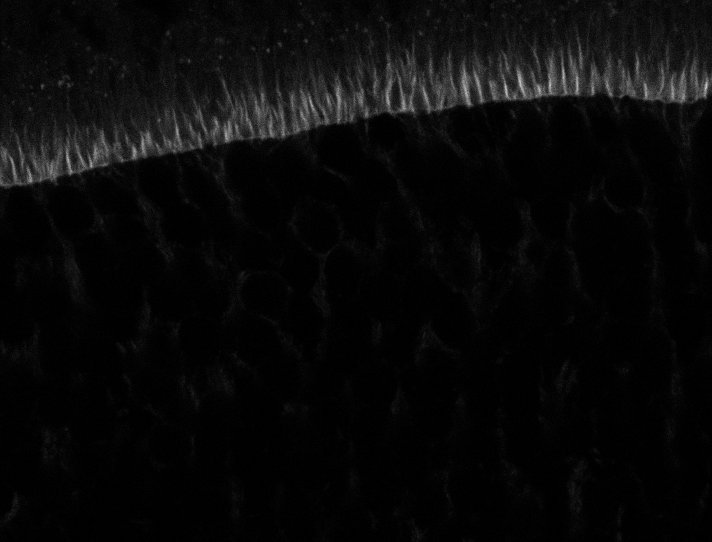

Actin